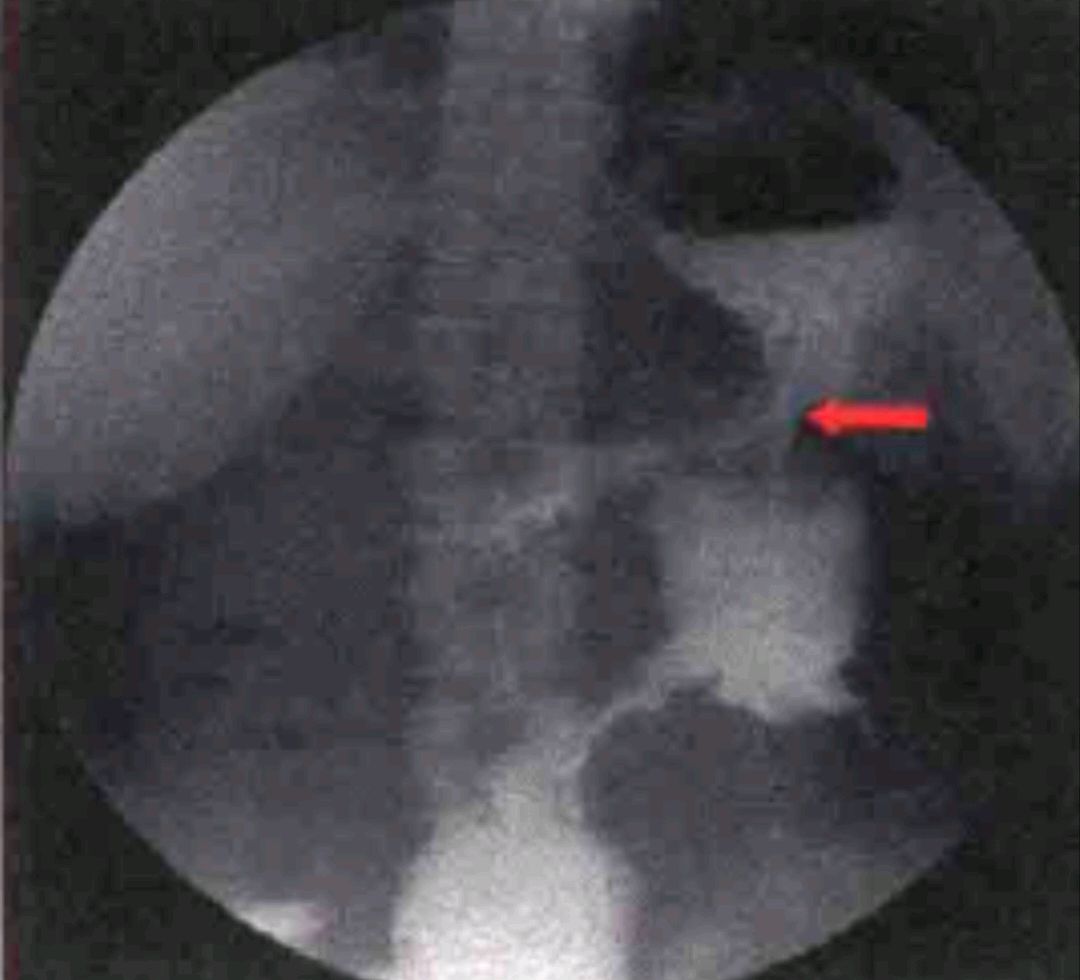

入院后为明确诊断,完善相关检查:血常规: WBC 10.10x 10*/L, Hb 50gL;白蛋白22g/L; 其余大致正常。腹部增强CT示:左上腹腔内结构紊乱,可见团状含气软组织密度影,增强后呈不均匀强化,边界不清,局部与胃体部分界不清, 似与横结肠及降结肠相通,病灶周围可见游离的气体影,相邻脂肪间隙模糊(图箭头所示为疑似的胃结肠瘘)。上消化道造影提示:胃体部大弯侧不规则龛影、造影剂进人横结肠,考虑占位病变、并胃-结肠瘘形成可能大。结肠造影显示:考虑占位病变降结肠近脾曲管腔狭窄、可疑充盈缺损,造影剂未通过并梗阻性表现可能大。胃镜检查:胃体小弯侧偏前壁巨大深溃疡,见污秽苔,透过瘘管可见横结肠内粪便,周围黏膜明显充血水肿,组织易出血。病理结果考虑胃体小弯侧胃黏膜腺癌浸润。考虑该例患者肿瘤分期晚,可能难以达到根治性切除,术前营养状况及基础条件差,入院时血常规、血生化示血红蛋白42g/L、白蛋白22 g/L,存在重度贫血及低蛋白血症;术前输注同型红细胞10 U,血红蛋白上升至106g/L,同时经过术前积极的全肠外营养支持治疗后营养状况有所好转,白蛋白35 g/L,患者诊断胃癌明确,有手术指征,未见明显手术禁忌症,遂行了姑息性远端胃大部切除术、横结肠部分切除术(近端造口,远端封闭)、胃空肠吻合(Roux- -en-Y)、空肠-十二指肠侧侧吻合术。术中探查见胃体前壁近大弯侧可触及约8 cm质硬肿物,肿物侵及横结肠并形成胃结肠瘘。胃周及后腹膜可触及多枚质硬肿大淋巴结,部分融合固定,切除病灶后行胃空肠吻合( Roux- -en-Y)。病理提示胃壁全层低分化腺癌浸润,脉管内见癌栓,术后第一天进流质饮食,逐步过渡半流质,术后一周出院。